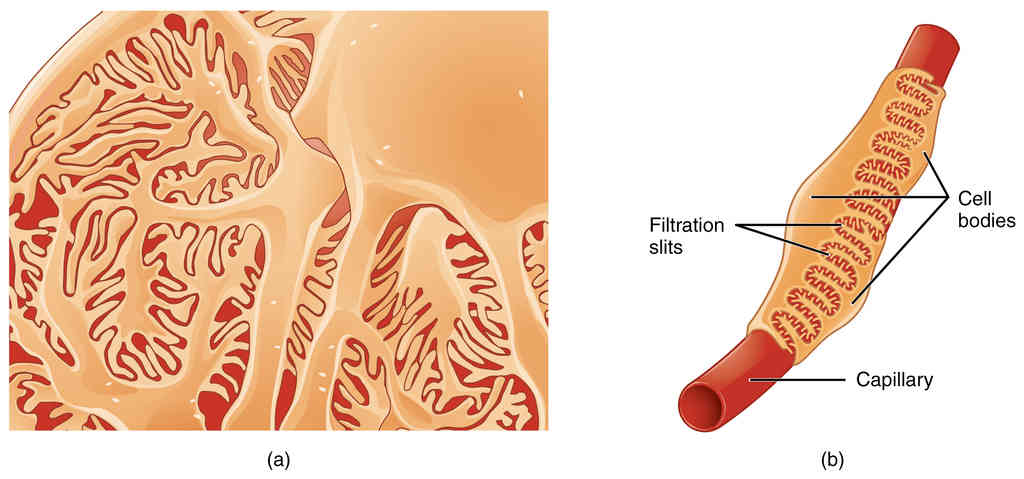

This page is under construction. For now, it is just a resource of the images found in the OpenStax Anatomy and Physiology Handbook. It wil slowly change into a revision tool. Each slide has a number. Use this to refer to the slide. When completed, it will have an unlabelled section, with labelled slides in parallel. On the unlabelled slides, write your answer and use the labelled slide to assess yourself. Keep track by also noting the number on each slide. Improvement at each attempt is important, more so than full marks on a first attempt.